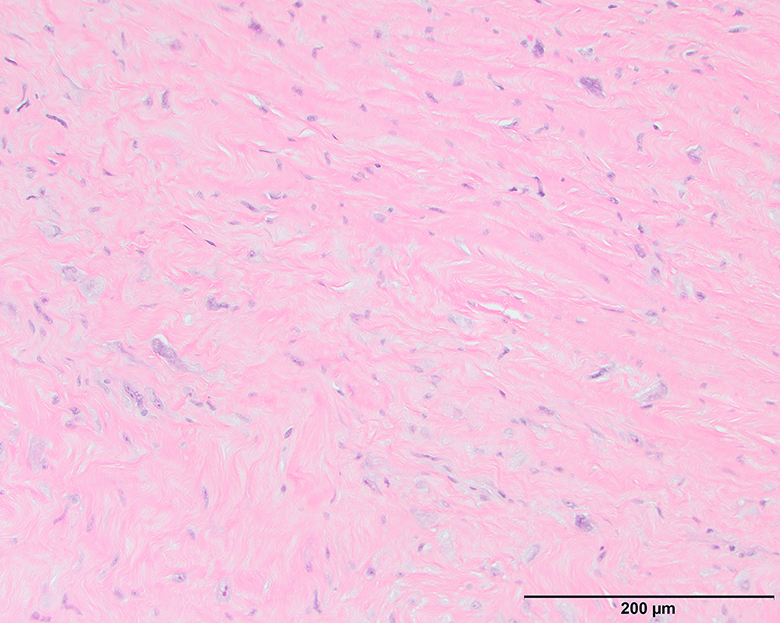

Microscopic (histologic) images

Contributed by Michael Clay, M.D., Melanie Bourgeau, M.D. and AFIP

Morphologic variability:

Microscopic (histologic) description

- Depends on subtype, generally composed of mature fat with variably sized adipocytes and bands of fibrotic stroma containing spindle cells with enlarged, hyperchromatic nuclei

- Can be markedly atypical

- Cellularity is low and mitotic figures are uncommon

- Atypical cells are more commonly found in fibrous septa and in a perivascular distribution

- Sclerosing subtype

- Second most common subtype

- Predilection for retroperitoneal or paratesticular location

- Collagenous fibrous tissue with scattered adipocytes and atypical multinucleated stromal cells

- Scant lipogenic component may be missed in small samples